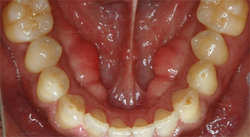

では「良い咬み合わせ」とはどういう状態をいうのでしょうか?

歯は物を咬むための道具であり、その歯を動かしているのは筋肉です。

筋肉が動いて物を咬もうとしたときに、ちょうど良い場所に歯がなければ、筋肉は余計な力を使ったり、歯に余計な負担がかかったりするのです。

切れ味の悪いハサミを使って物を切ろうとすると、腕に余計な負担がかかるのと同じことです。

「良い咬み合わせ」とは、そういった余計な力を使うことなく、自然に咬める状態という事になります。

具体的な治療は、それぞれの患者様にとって、「良い咬み合わせ」である場所に歯をつくるということになります。

患者様が動かすお口に合わせて歯の高さを揃え、上と下のはを咬み合わせる治療です。